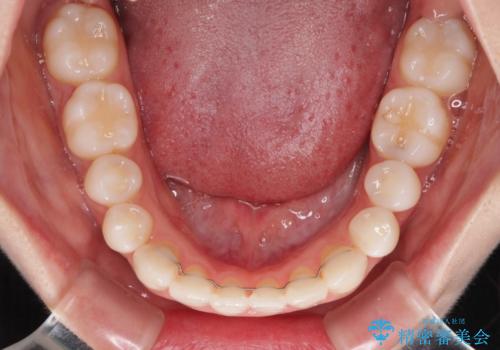

- クリアブラケット

- 2年

舌のトレーニングは、突出癖がなくなるまで必要であり、矯正治療後に突出癖が残ると、あっという間に隙間が空き、後戻りでデコボコとなってしまいます。